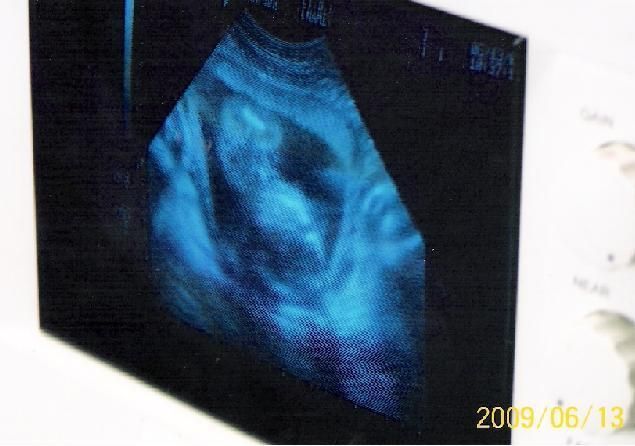

We arrived just in time as we were receiving the morning report. A young, attractive girl pulled onto the hospital lot. Daniel talked to her and brought her over to the new and improved ultrasound van. We came inside and were able to watch her approx 20 week old baby, presumably a boy, auditioning for his little life on the ultrasound screen. She was broken; tears of joy rolled down her cheeks. We listened to the little heartbeats and went over resources and physician follow-up. She thanked us for being there and promised to keep in touch.